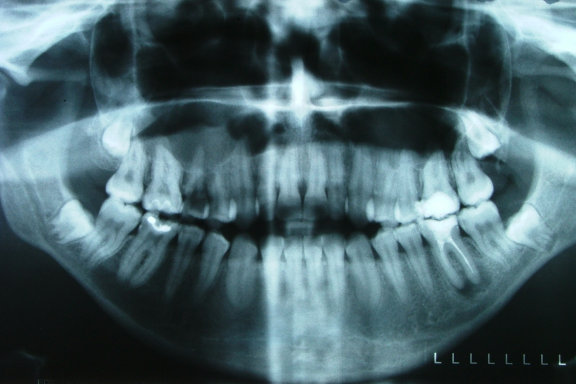

Rentgensko slikanje zob

Za dvo ali tro dimenzionalno rentgensko slikanje zob vam priporočamo GreenCT v Novem mestu.